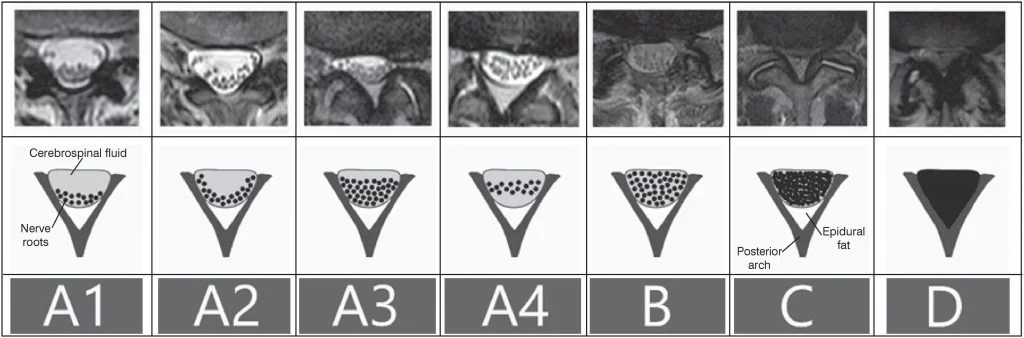

Η διάγνωση συνήθως μπαίνει με την αξονική τομογραφία και τη μαγνητική τομογραφία. Η αξονική τομογραφία δείχνει πολύ καλά την ποιότητα των οστών ενώ η μαγνητική τομογραφία δείχνει εξαιρετικά ποιά νευρικά στοιχεία πιέζονται και βοηθά στην σωστή εκτίμηση της στένωσης (Εικόνα 3). Η μαγνητική τομογραφία είναι η πιό σημαντική εξέταση σ’ αυτή την περίπτωση.